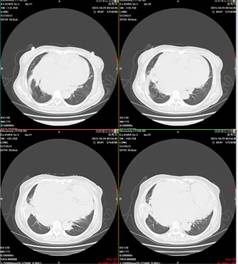

肺部CT示右肺下叶基底段见斑片状稍高密度,边界清晰。考虑:考虑右肺下叶炎症,不除外占位性病变。

(复查肺增强CT,炎症部分较前有所吸收,未发现肺部占位性病变)